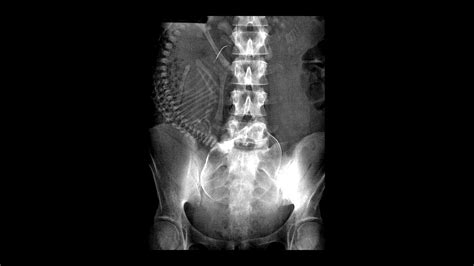

- Pelvic X-Ray: A general X-ray of the pelvic region that can help identify fractures, tumors, or other abnormalities in the bones and soft tissues.

- Evaluating Anatomical Abnormalities: Conditions such as uterine fibroids, ovarian cysts, and other anatomical issues can be diagnosed using Sex X Ray technology.

| Anatomical Abnormalities | Uterine Fibroids, Ovarian Cysts |